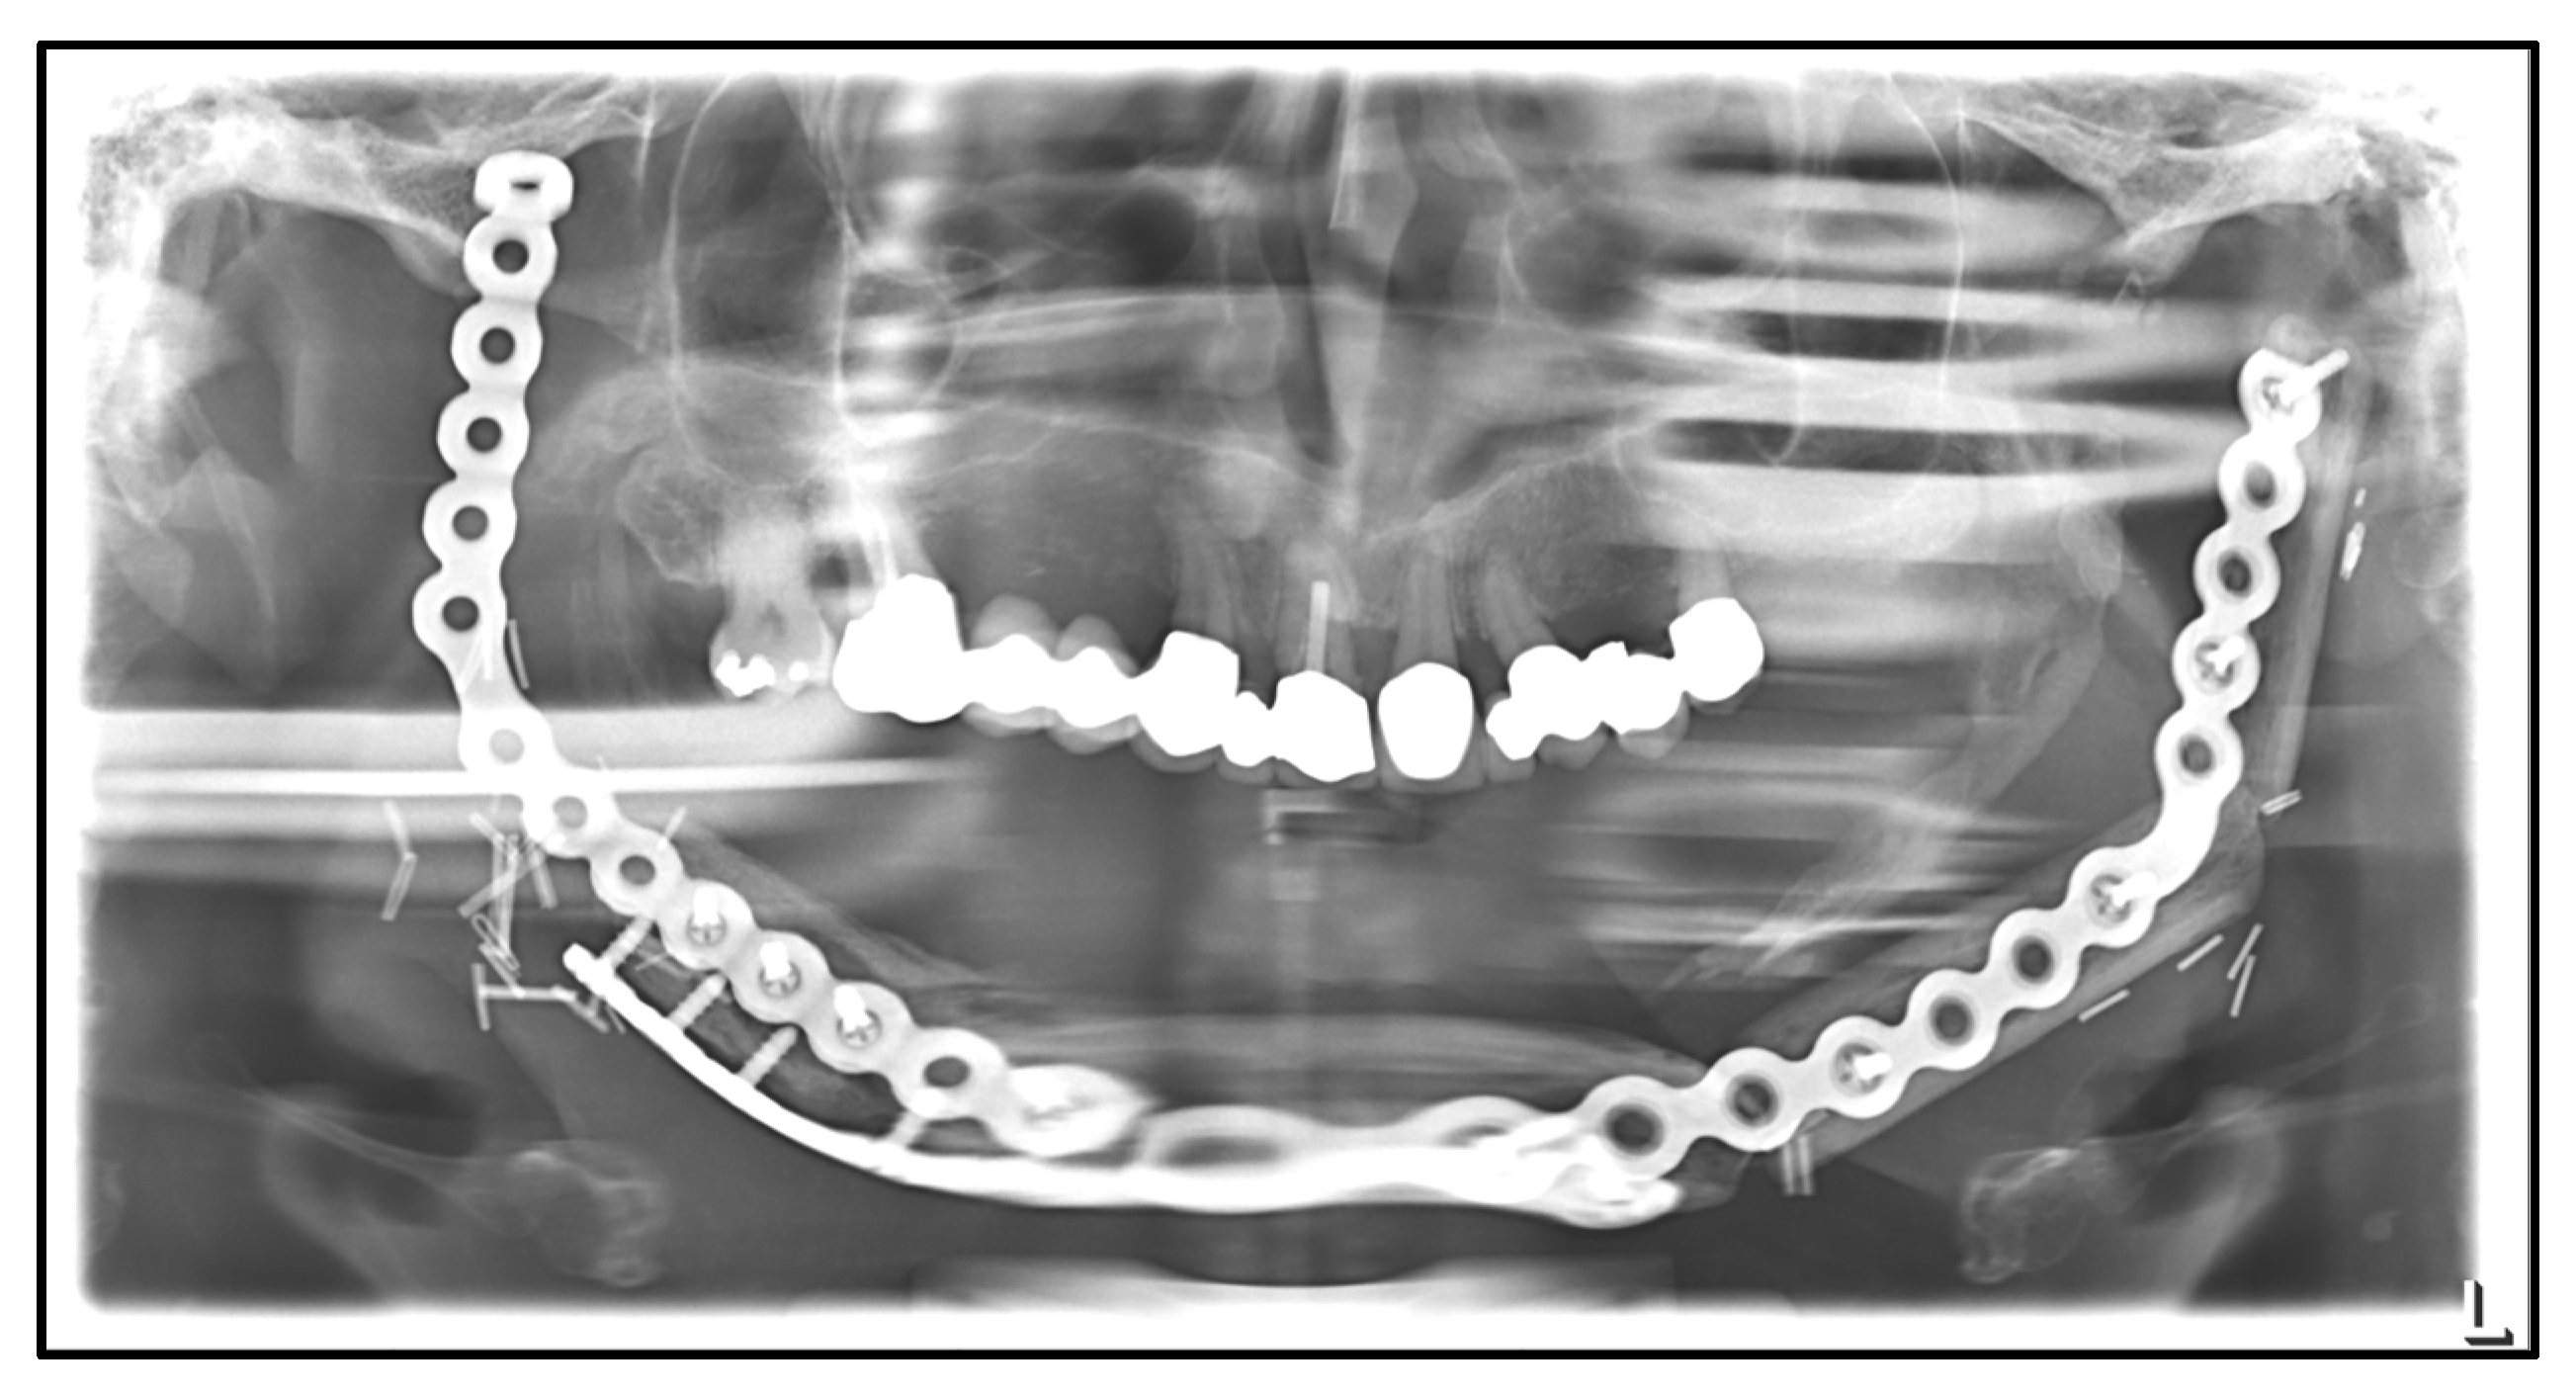

| April 2020: | Partial mandibular resection from the left to the right mandibular angle, CAD/CAM-assisted reconstruction using a free fibular graft and PSI, temporary tracheostomy. In the course: development of aspiration pneumonia treated with piperacillin and tazobactam 4.5 g for 8 days. |

| April 2021: | Placement of four dental implants in the neo-mandible for dental rehabilitation. |